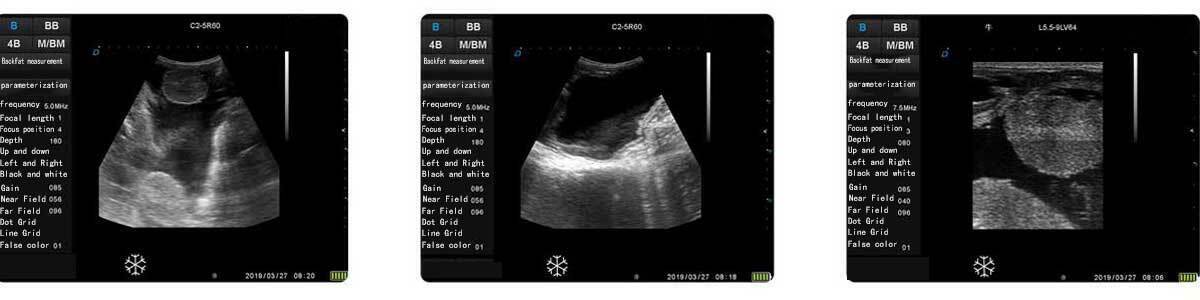

4.Diverse Measurement Functions

Conventional Measurement: Distance, Perimeter-Ellipse, Perimeter-Trajectory, Area-Ellipse, Area-Trajectory

Specialized Measurement: Abdominal, Cardiac, Obstetric, Superficial